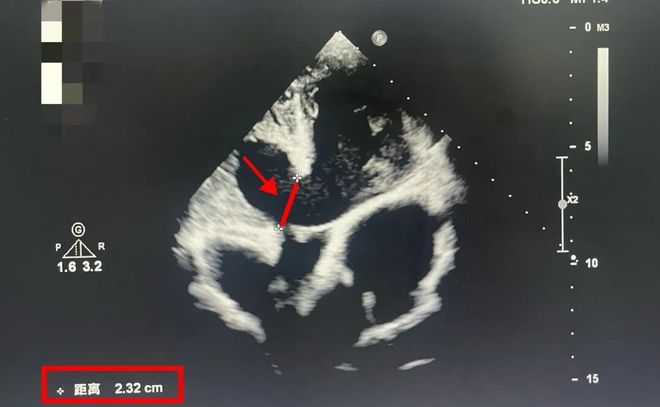

那时的李小还不知道他的心脏缺损已达22毫米。

通常室间隔缺口超过5毫米就需要手术修复。而他情况远超正常指标,心功能也已下降到低于50%的水平。

这意味着再拖延下去可能导致严重的心脏衰竭,影响寿命。